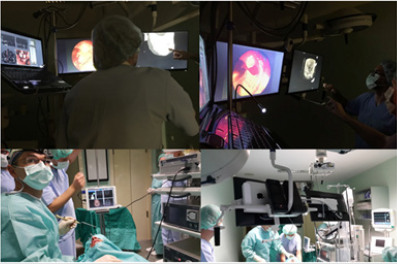

Thus, technology should deliver productivity advances which need capable interdisciplinary developers in the fields of, among others, IT and medicine that would help in shaping in the educational approach. This project of „contactless non-invasive sinus surgery in rhinology” [2,6,10], once completely realized, would help overcome current trends of increasing technological change, because by adopting different approaches and frameworks in such distributed, augmented virtual labs, physicians/surgeons could adapt to new technologies much faster with less stress in any OR, enabling an easier transition from the stages of education to the workforce/ OR. This newest „medical strategy“ could be an important step to enhance surgeons’ capacities and increase their overall success because the real and virtual objects definitely need to be integrated in the surgical field [12](Figure 1), for a number of reasons, such as orientation in the operative field where ‘overlapping’ of the real and virtually created anatomic models is inevitable [13-15].

Figure 1: Examples of medical data analysis in the real time with enabled virtual reality in order to help the surgeon in decision making during the surgery. We used OsiriX MD (DICOM viewer, certified for medical use), Leap Motion (computer hardware sensor device that supports hand and finger motions as input), and our specially designed software that integrates Leap Motion controller with medical imaging systems.